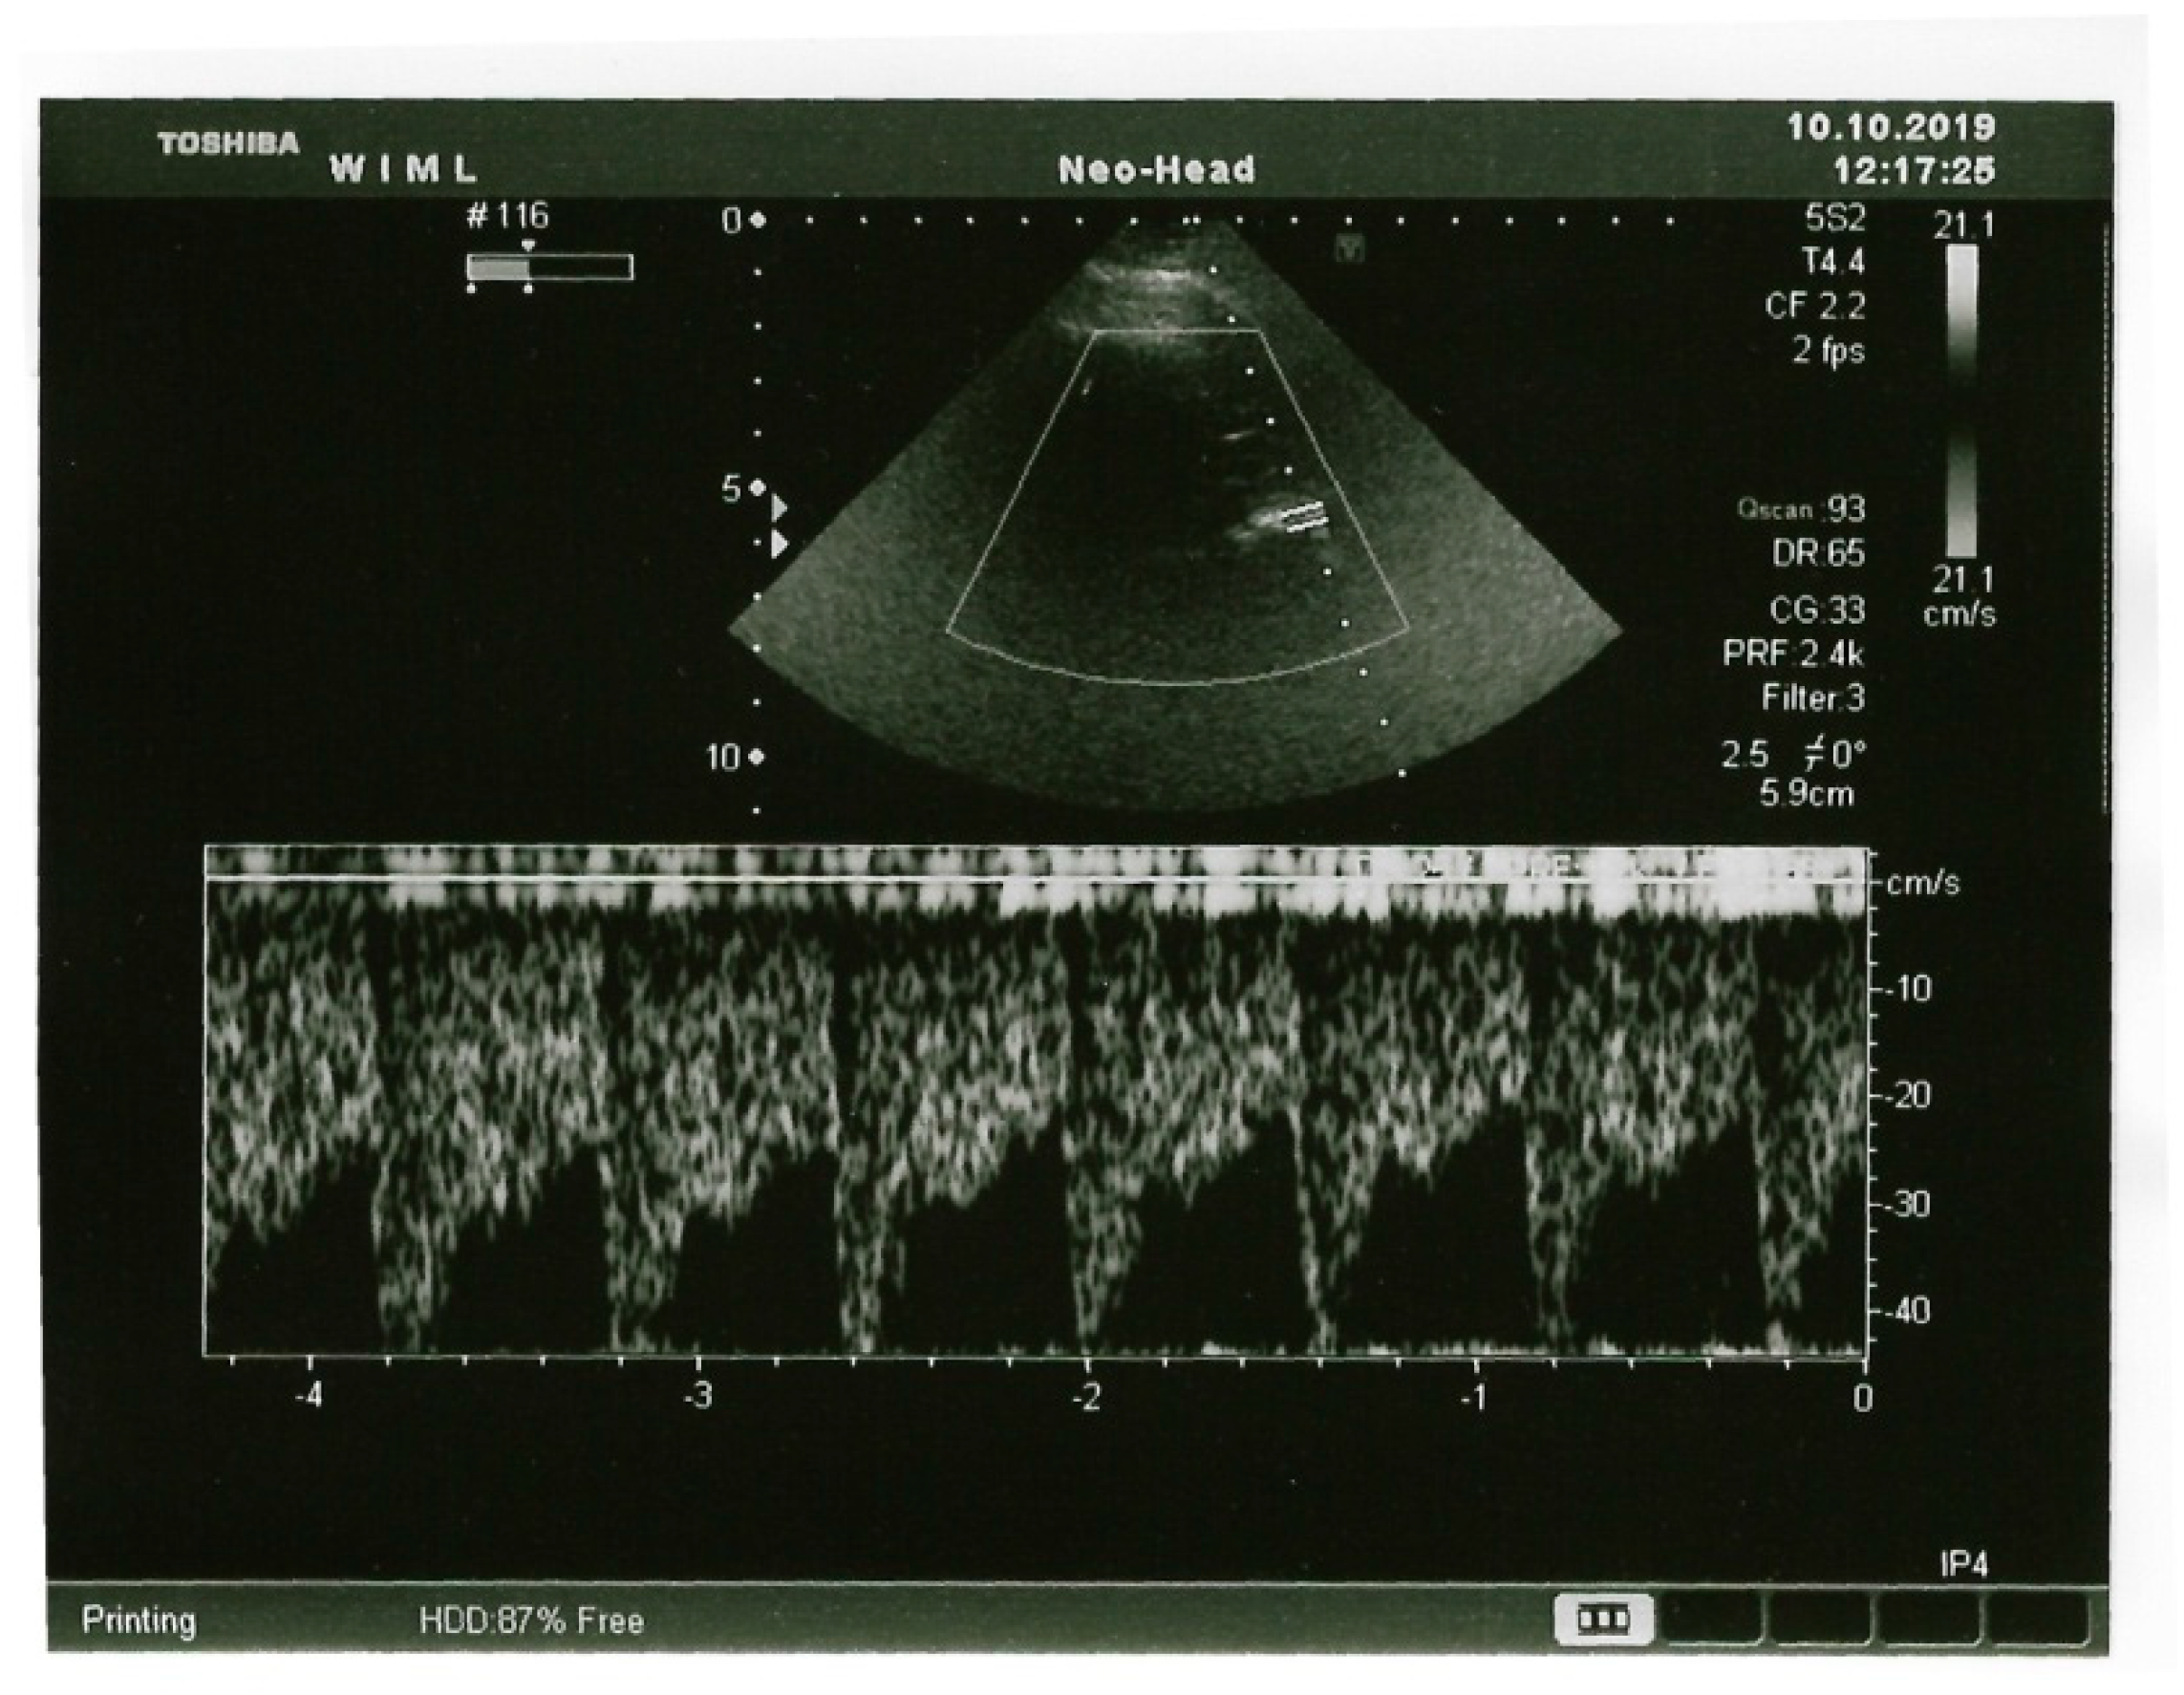

Aggressive and Autoaggressive Behaviors in Patients with Autism Spectrum Disorder in Correlation with Middle Cerebral Artery Flow Velocity

2. Materials and Methods

3. Results